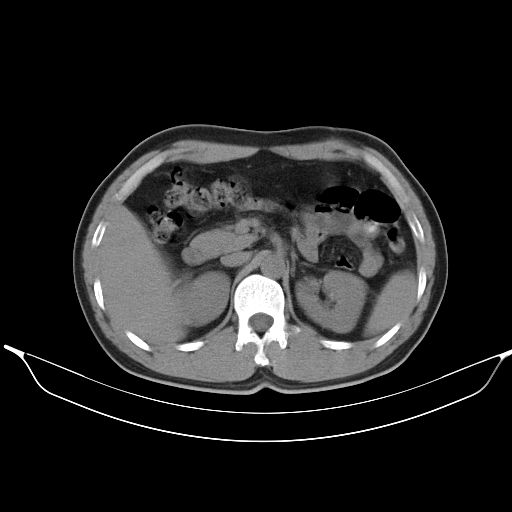

标题: CT25490:男,40岁,体检发现;无其它不适。 [打印本页]

标题: CT25490:男,40岁,体检发现;无其它不适。

考虑:1、过各敏性肺炎可能性大,建议定期复查。

2、轻度脂肪肝。

考虑右下肺周围性肺癌并肺内多发转移,纵隔淋巴结转移!

支持 !考虑右下肺周围性肺癌并肺内多发转移,纵隔淋巴结转移,(气管前腔静脉后,隆突下,主动脉弓下都有了)

1、均为转移,原发灶不在肺内。2、肺癌肺转移。